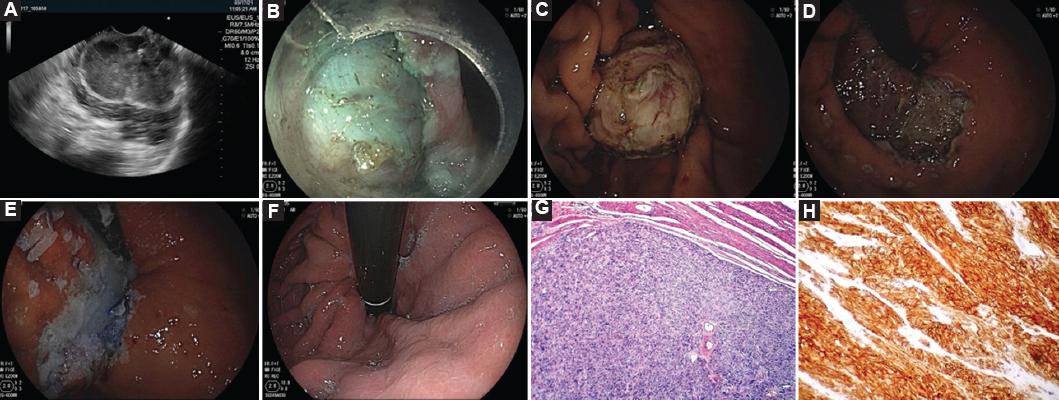

De acuerdo con el tamaño, la localización y las características de la lesión, se utilizó la misma técnica de DES que en las lesiones epiteliales, o se realizó la modificación con combinación con tunelización o REM (Fig. 4).

Figura 4 Disección endoscópica combinada con tunelización para la resección de un tumor subespitelial. A: lesión subepitelial dependiente de la cuarta ecocapa con degeneración quística y calcificaciones de 65 × 43 mm de diámetro. B: lesión submucosa expuesta. C: lesión disecada. D: lecho de resección. E: cierre de lecho quirúrgico con clips OVESCO y cianoacrilato. F: revisión 5 meses después de la disección endoscópica submucosa. G: histología con tinción de hematoxilina y eosina. H: inmunohistoquímica con CD-117 positivo.